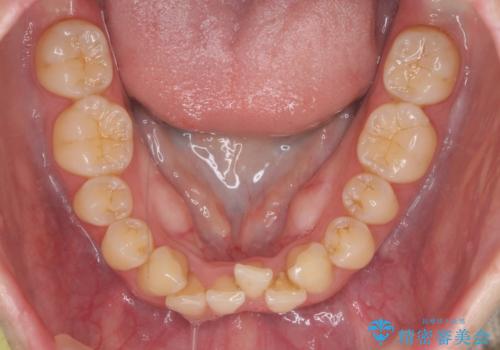

前歯のガタつき インビザラインで 下の前歯を1本抜歯

- 前歯のがたつきを主訴に来院。マウスピース矯正を希望されました。

治療にあたり、下の前歯を一本抜歯しています。

非抜歯で無理に治療をしようとすると、下の前歯の骨が薄く歯ぐきが下がったり、歯がぐらついたり、がたつきが完全にとれないリスクがあることを説明しました。

下の前歯が3本になるため、上下の正中は合わない仕上がりとなりますが、正中を合わせるには上下左右4本抜歯の上、ワイヤー矯正となってしまいます。

それよりは抜歯の数も少なく、メリットが大きいのではないかと説明し、選んでいただきました。